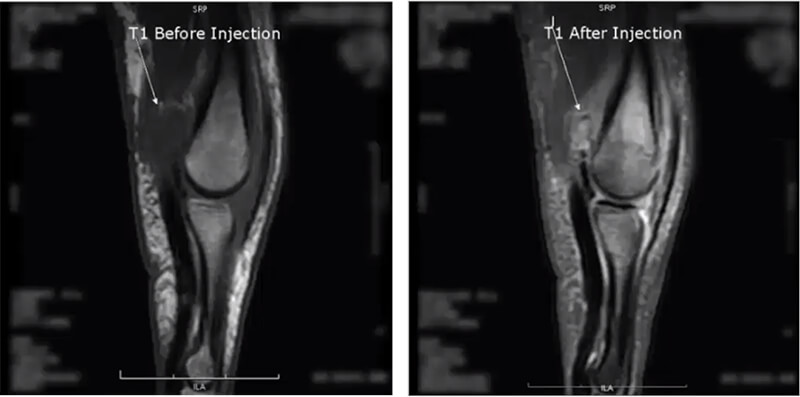

On the fourth image, we are evaluating Morton’s neuroma in T1 and we see that darkened area between two of the toes. Next, we run a T2 fat sat, which suppresses the fat and allows us to see true pathology. Then we run the post-contrast as a T1 injected fat sat. Again suppressing the fat, but notice the contrast enhancement of the lesion now compared to the first T1.

The last image is a finger in the sagittal plane. On the T1 before the injection, we see a dark area, mostly likely pathological fluid, and after the contrast injection again run as a fatsat which is usually the case with extremity images post-contrast, we now see there is pathology hidden within the fluid. This is some form of a lesion which may not have been noticed had contrast not been used.